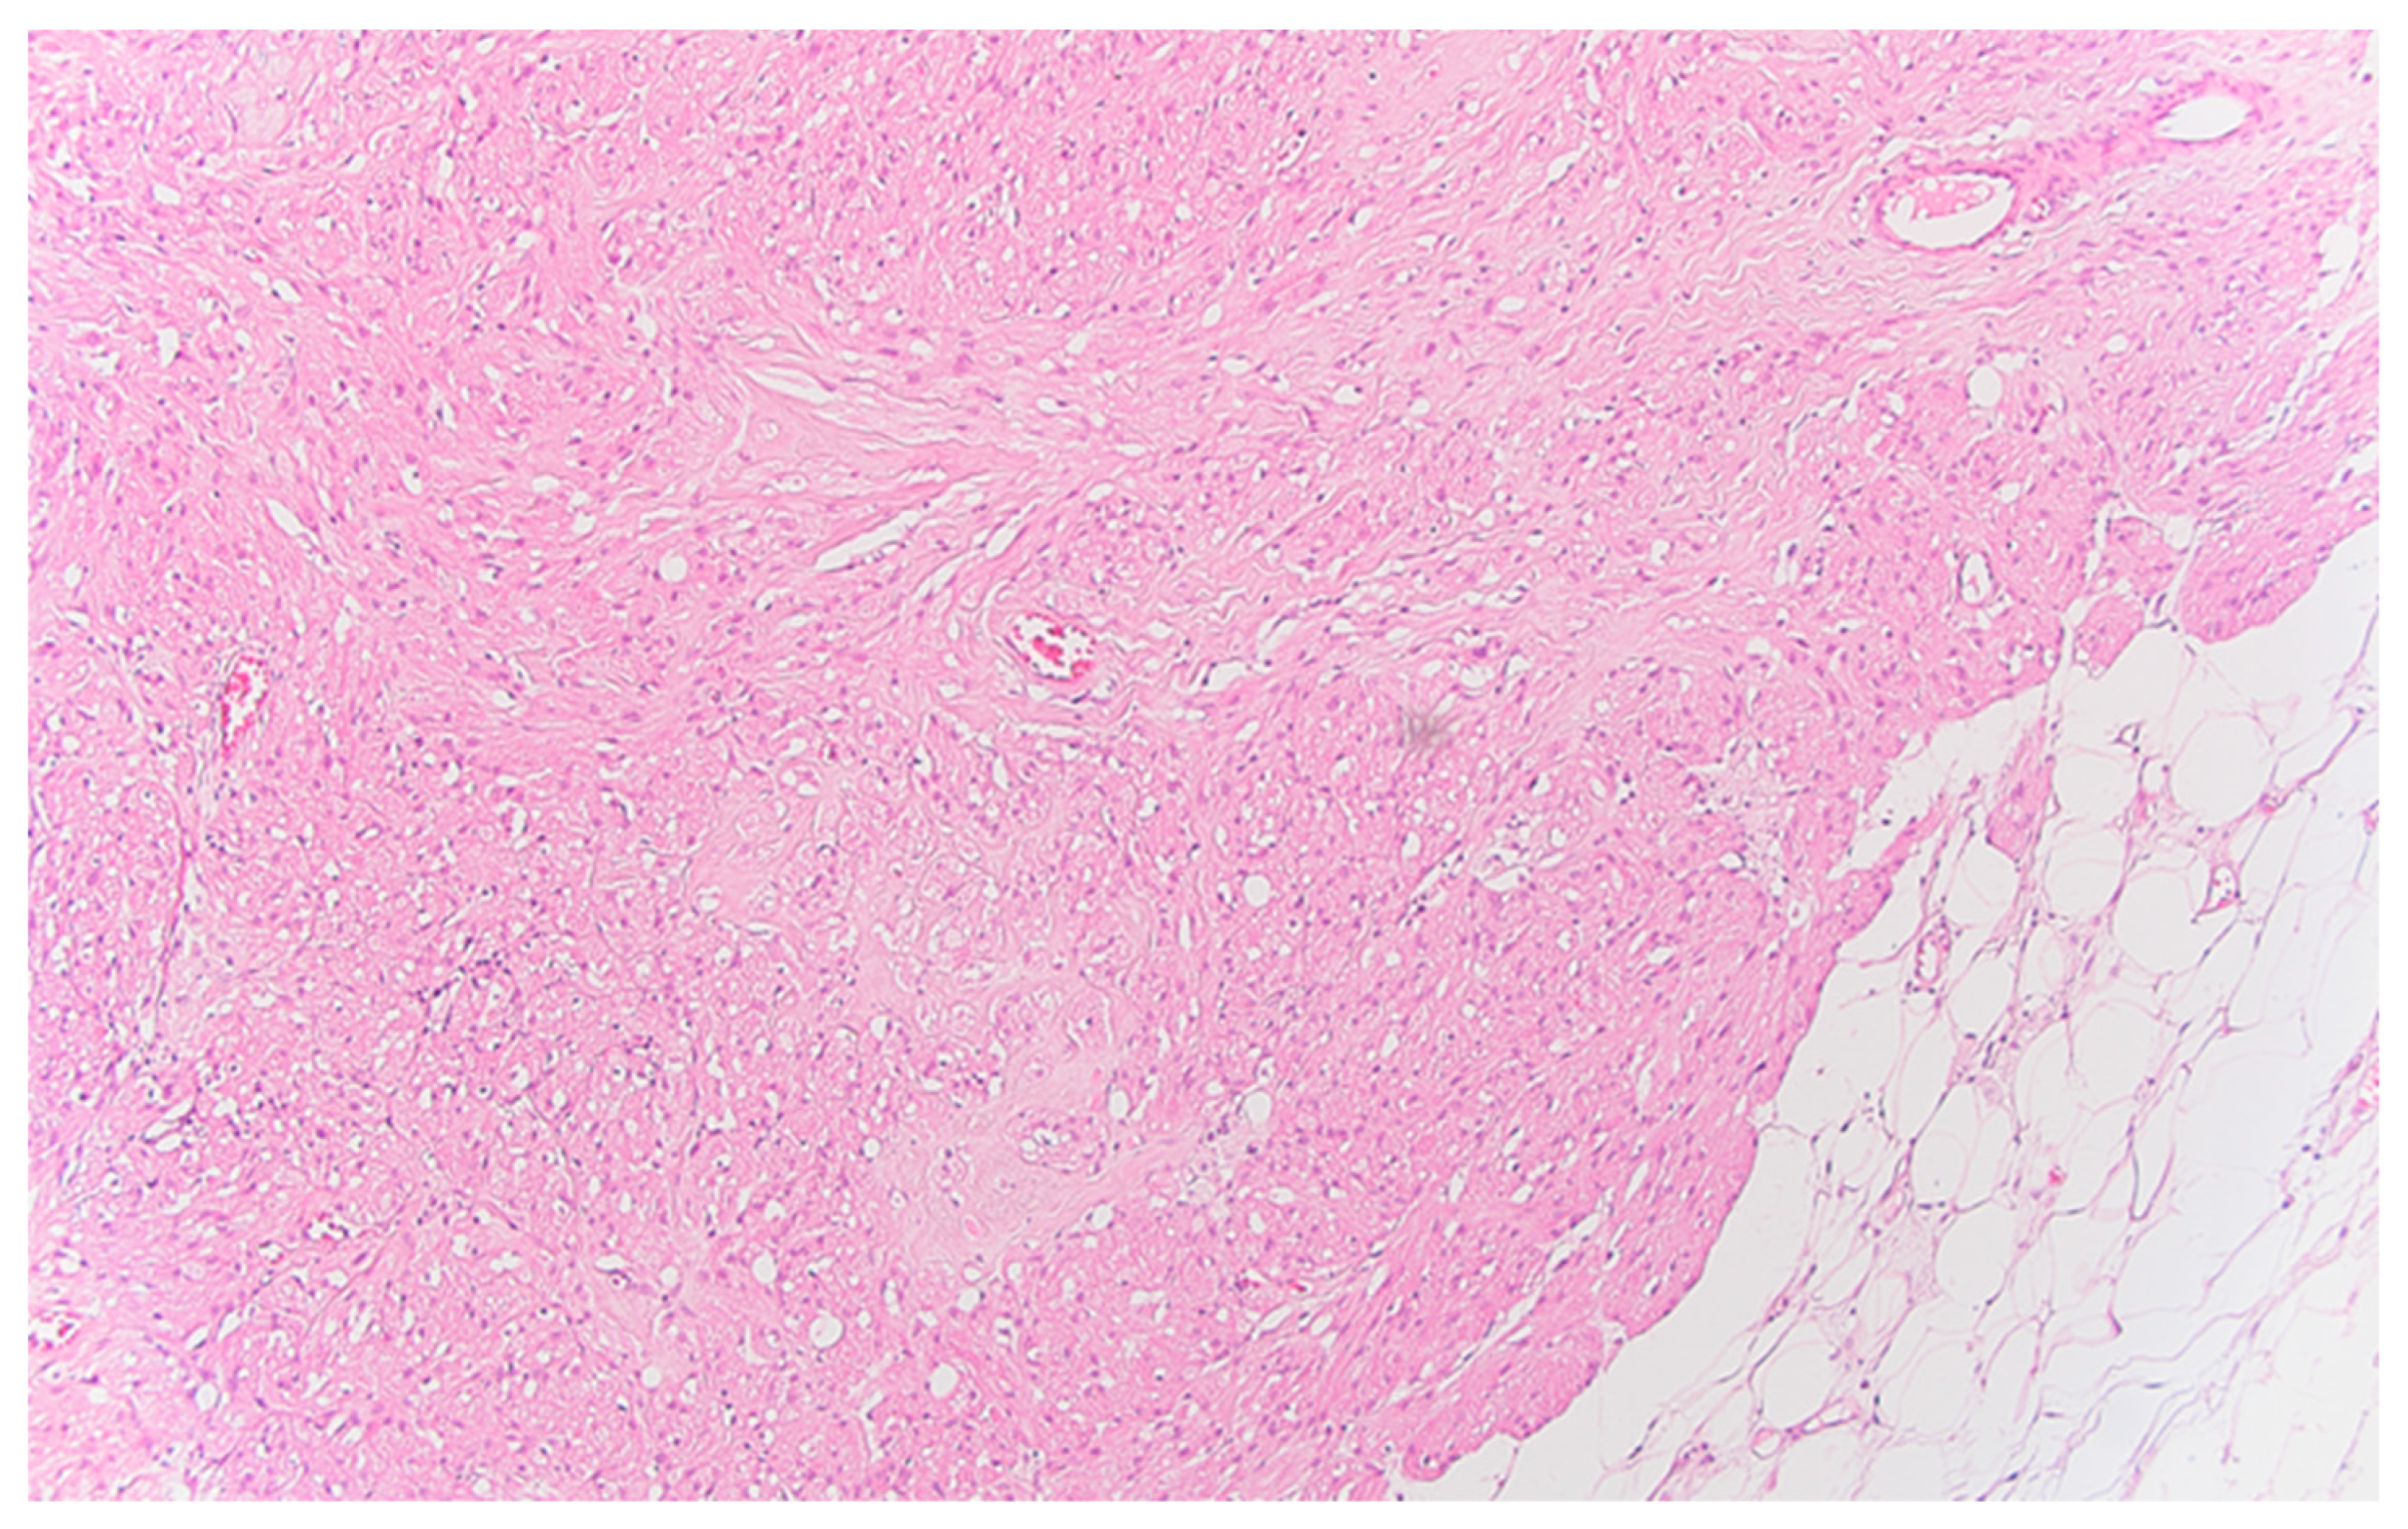

Figure 4. Peritoneal granular cell tumor nests and fascicles of large polygonal cells with abundant, eosinophilic, granular cytoplasm, HE x100.

Well delineated from the previously described malignant epithelial-glandular tumor, large polygonal cell nodules, with abundant, eosinophilic, granular cytoplasm, hyperchromatic or vesicular nucleolated nuclei are found in the submucosa of the cecum and the visceral peritoneum of the ascending colon (Figure 4); without cyto-nuclear atypia, without tumor necrosis. These tumor nodules develop in the vicinity of nerve fibres.